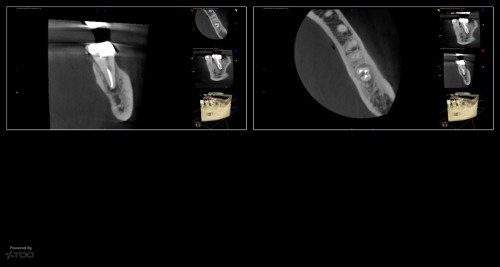

Collage-232332-Page00

This was a finish from last week.  The largest file used was a 20.  The innovation of the heat treated files allow us to be more conservative from the access to the instrumentation.